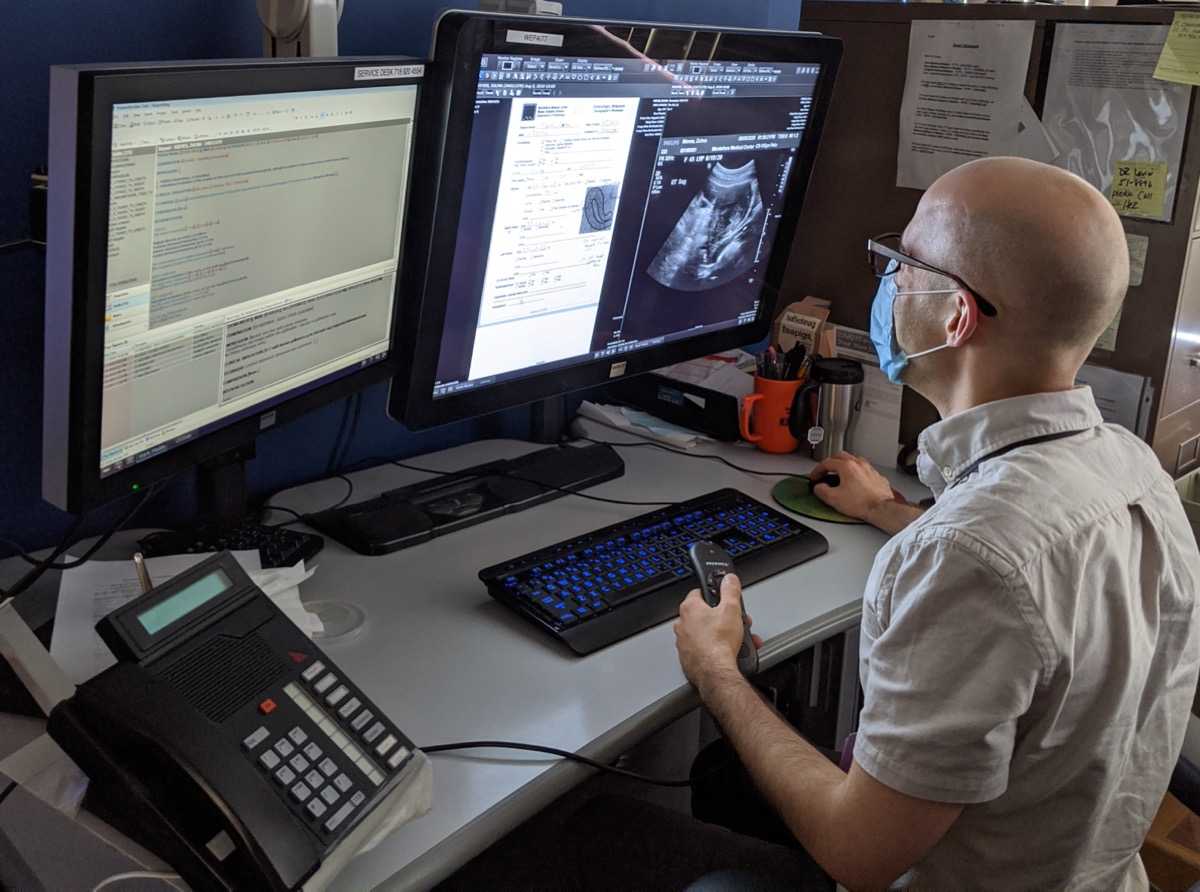

We prepare our residents for their careers as physicians with a training that emphasizes hands-on teaching and graded independence. Our Diagnostic Radiology Residents learn to dictate cases independently through apprentice-style teaching at the workstation and an extensive didactic teaching curriculum, while our Integrated Interventional Radiology Residents gain valuable clinical experience by practicing in multiple environments and managing patient care. Each resident sees a high volume of cases, including severe cases in our NCI Cancer Center and Liver Transplant Program. Specialty collaboration, direct feedback, collegiality and research opportunities allow every resident to maximize their potential.

Moses Campus is the primary teaching site for our training programs. Our sub-specialty reading rooms serve as a hub for active clinical care and teaching, and support tertiary-level referral programs throughout the entire breadth of adult and pediatric medicine. In addition to specialized reading rooms, residents have full access to our resident library and a newly renovated resident lounge, and are invited to take advantage of our 3D imaging lab. Resident conferences are presented in-person from Binswanger Auditorium, although we electronically simulcast lectures and conferences from Moses to all our clinical sites. Resident learning is enhanced through participation in a range of interdisciplinary tumor boards and research programs.